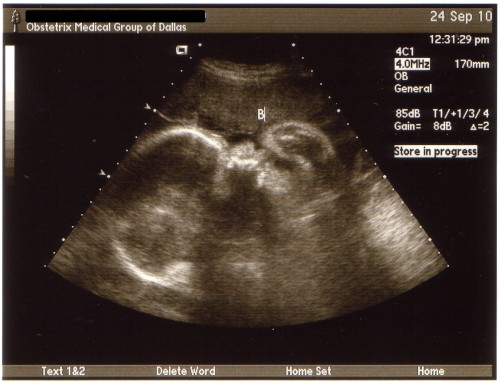

Here are some pictures of the boys’ profile from Friday…

Baby A - 33 weeks

Baby B - 33 weeks

On Friday we had our 33 week appointment with the perinatologist and our monthly growth scan of the boys. Everything looked great with the boys and they are growing just like they should, each of the boys gained a pound from 3 weeks ago! Baby A (Hayden) is now up to 4 lbs 3 oz and Baby B (Ian) is 3 lbs 14 oz….that’s 8 pounds of baby. The boys were both doing their practice “breathing” and moving around so we didn’t have to “taser” either of the boys this time. Baby A was being lazy again and took a little poking to get him to move around but he eventually did. Baby A is still head down (just like he has been for the last 8 months) and his body just kinda goes all along my right side while baby B is all curled up in a little ball. They couldn’t really tell us what position he was in, he wasn’t exactly breech or transverse, he was just kinda curled up. I’m going to guess he will be the one that likes to be swaddled up tightly. We will go back in another 4 weeks for our last growth scan but I’m kinda hoping we don’t make it to that appointment because they will already be here by then…one can hope, right?

We talked with the perinatologist and he was happy with their weights and amount of amniotic fluid. My cervix was the same as it was last Friday when I was at my OB’s office and he said as of right now the contractions aren’t doing a whole lot to it but that could change over night. He agrees with my OB that I should have a c-section at 37-38 weeks and not wait for 39 weeks like the hospital wants me to do. He said if I go into labor before next Thursday/Friday he (or my OB) would try to stop the labor and give me steroid injections to help give the boys’ lungs a boost. But one I reach 34 weeks (next week) the boys would do well enough if they were born that he wouldn’t stop labor. He said they would more than likely have to spend about a week in the hospital…but you never know until they are here. I will see my OB on Friday and then every week until they are here….which hopefully won’t be too much longer. I am so ready for them to get here….lack of sleep and all! But, as much as I want them here I hope they wait at least another week or 2, they need to grow a little bit more.